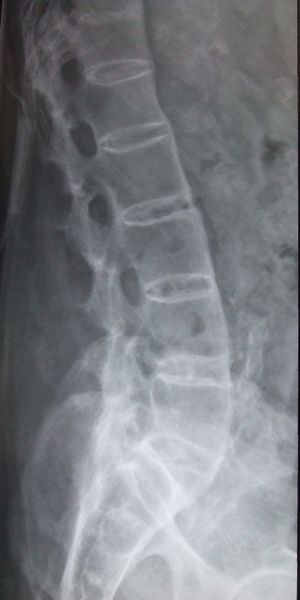

التهاب الفقار المقسط أو اللاصق Ankylosing spondylitis باليونانيةankylos, stiff; spondylos, vertebrae), تسمى قديماًBekhterev's disease, Bekhterev syndrome, و Marie-Strümpell disease هو نوع من التهاب المفصل في العمود الفقري. وهو يسبب تورماً بين الفقرات، والفقرات هي الأجزاء الأسطوانية التي تكون العمود الفقري، كما يسبب تورماً في المفاصل بين العمود الفقري والحوض. إن التهاب الفقار المقسط أو اللاصق هو أحد أمراض المناعة الذاتية. إن الجهاز المناعي المسؤول عن حماية الجسم من العدوى يقوم بمهاجمة أنسجة الجسم نفسها في حالة أمراض المناعة الذاتية. ويكون التهاب الفقار اللاصق أكثر انتشاراً وخطورة عند الرجال. وكثيراً ما يكون مرضاً ينتقل عن طريق الوراثة.[1]

ومن أعراضه المبكرة ألم الظهر والتيبس. وهي تبدأ غالباً في مرحلة المراهقة المتأخرة أو أوائل البلوغ. ومع مرور الوقت يمكن لالتهاب الفقار اللاصق أن يؤدي إلى التحام الفقرات مما يقيد حركتها. يمكن أن تتفاقم الأعراض كما يمكن أن تتراجع أو تختفي تماماً. إن هذا المرض غير قابل للشفاء، لكن الأدوية يمكن أن تهدئ الألم والتورم والأعراض الأخرى. ويمكن أن تكون التمارين الرياضية مفيدة أيضاً.

يبدأ التهاب الفقار المقسط في صغار البالغين بألم مبهم في أسفل الظهر، ويبوسة مديدة تالية للراحة تتحسن جزئياً بالحركة والتمارين الرياضية. ينتشر الألم إلى الاليتين والقسم الخلقي من الساقين. كما يحدث ألم في القفص الصدري بإصابة المفاصل الغضروفية المركزية فيه، وقد يكون لهذا الألم صفات جنبية، ويظهر الألم أيضاً في مفاصل قبضة القص Manubriosternal والمفاصل القصية الترقوية. إن التهاب ارتكازات الأربطة والأوتار عرض بارز وقد يكون العرض الأول. وينجم الألم عن التهاب الأصابع Dactylitis ' أو وتر أشيل، أو اللفافة الأخمصية، أو عرف الحرقفة iac أ I Crest. تكون الإصابة المفصلية بشكل الام مفصلية، أو التهاب مفاصل عديد، يصيب المفاصل الزليلة الدانية وبشكل غير متناظر كالكتفين والمرفقين والركبتين ونادرا المفاصل الصغيرة القاصية. وتترافق هذه الإصابة بيبوسة صباحية مديدة وأحياناً بتورم الا أنه من غير الشائع حدوث إصابة مفصلية تاكلية شديدة.

يحدث التهاب العنبية الأمامي في حوالي ربع المرضى، ويتظاهر بألم واحمرار وخوف من الضياء، وتكون هذه الإصابة نوبية، وحيدة أو ثنائية الجانب. يبدي الفحص السريري نقصاً في حركية العمود الفقري، مع فقد تام أو جزئي للقعس القطني الفيزبولوجي، وزيادة في الحدب الظهري. أما المظاهر المتأخرة فتشمل تحدد حركة جدار الصدر في الشهيق العميق (أقل من 2.5 سم) مع انحناء تدريجي، وثبات العمود الفقري والرأس في وضعية العطف. ويمشى المريض جاراً قدميه Shuffling Gait مع تفاوت شدة إصابة المفاصل المحيطة.[2]